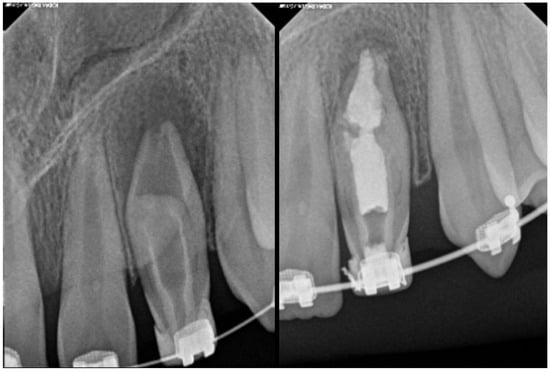

| Type II | Moderate to high risk of pulp involvement | CBCT recommended to assess depth and pulp communication | Preventive sealing or minimally invasive restoration If pulp compromised, vital pulp therapy or root canal treatment depending on health state of pulp | Good to fair prognosis if depth is within coronal third and detected early Radiographic follow-up needed to monitor healing |